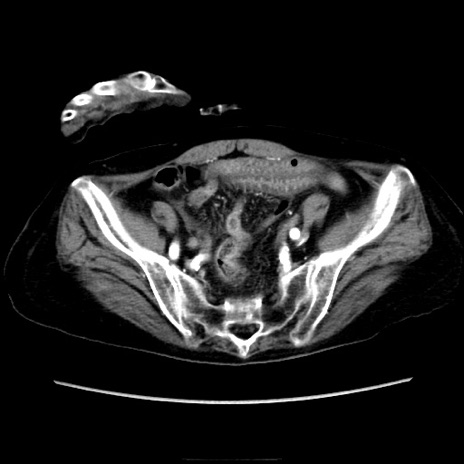

症例40(横断像)

【症例】90歳代女性

【主訴】腹痛・嘔吐

【現病歴】 食欲低下、嘔吐があり昨日他院受診。肺炎と診断され入院となる。入院後より腹部全体に圧痛あり。胃管留置され経過みていたが、症状持続するため、

当院転院となる。

【既往歴】胸椎圧迫骨折、胆石症

【身体所見】腹部:中央に激痛あり、圧痛あり、反跳痛不明

【データ】WBC 17100、CRP 18.82

横断像